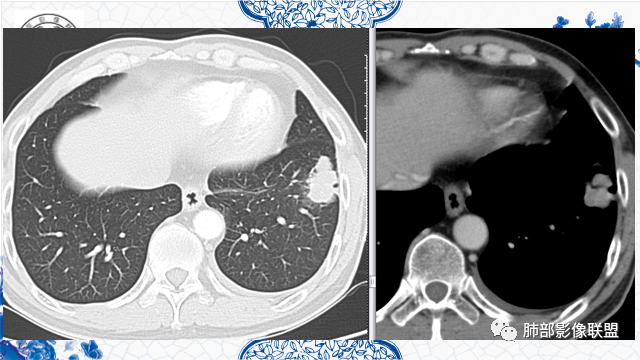

左下叶不规则实变,有平直及u型凹陷,胸膜糊墙,不均匀强化,其内可坏死灶,肿块内缘起始部可见钙化灶,病史较长,虽有胃肾肿瘤史,但影像表现及病灶走行(爬行征)均不支持转移,综合分析考虑炎性肉芽肿,OP并脓肿,其次考虑TB,留个尾巴鉴别腺癌

左肺下叶前基底段肿块,分叶状,边缘平直凹陷,部分膨隆。支气管进入后截断,宽基底与胸膜相连,内部坏死,周围有小卫星灶,强化见坏死区周围环形高密度,首先考虑良性,肉芽肿,结核?鉴别腺癌。

既往胃肾肿瘤。左下肺病灶直边,凹陷,支气管进入并有截断,宽基底与胸膜相连,内部有囊圆形坏死,旁边有卫星灶,考虑良性,肉芽肿,恶性,腺癌转移待除